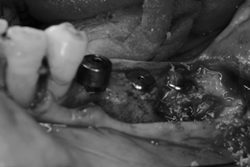

![]() |

インプラント埋入時も骨再生治療(GBR)を併用しないといけませんでした。